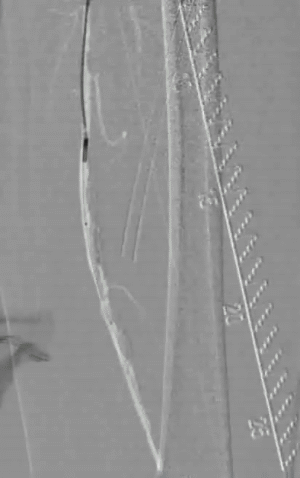

术前造影:右侧股浅动脉中段重度狭窄、远端闭塞,膝下仅腓动脉通畅。

图片图片图片

手术策略:DA+DCB